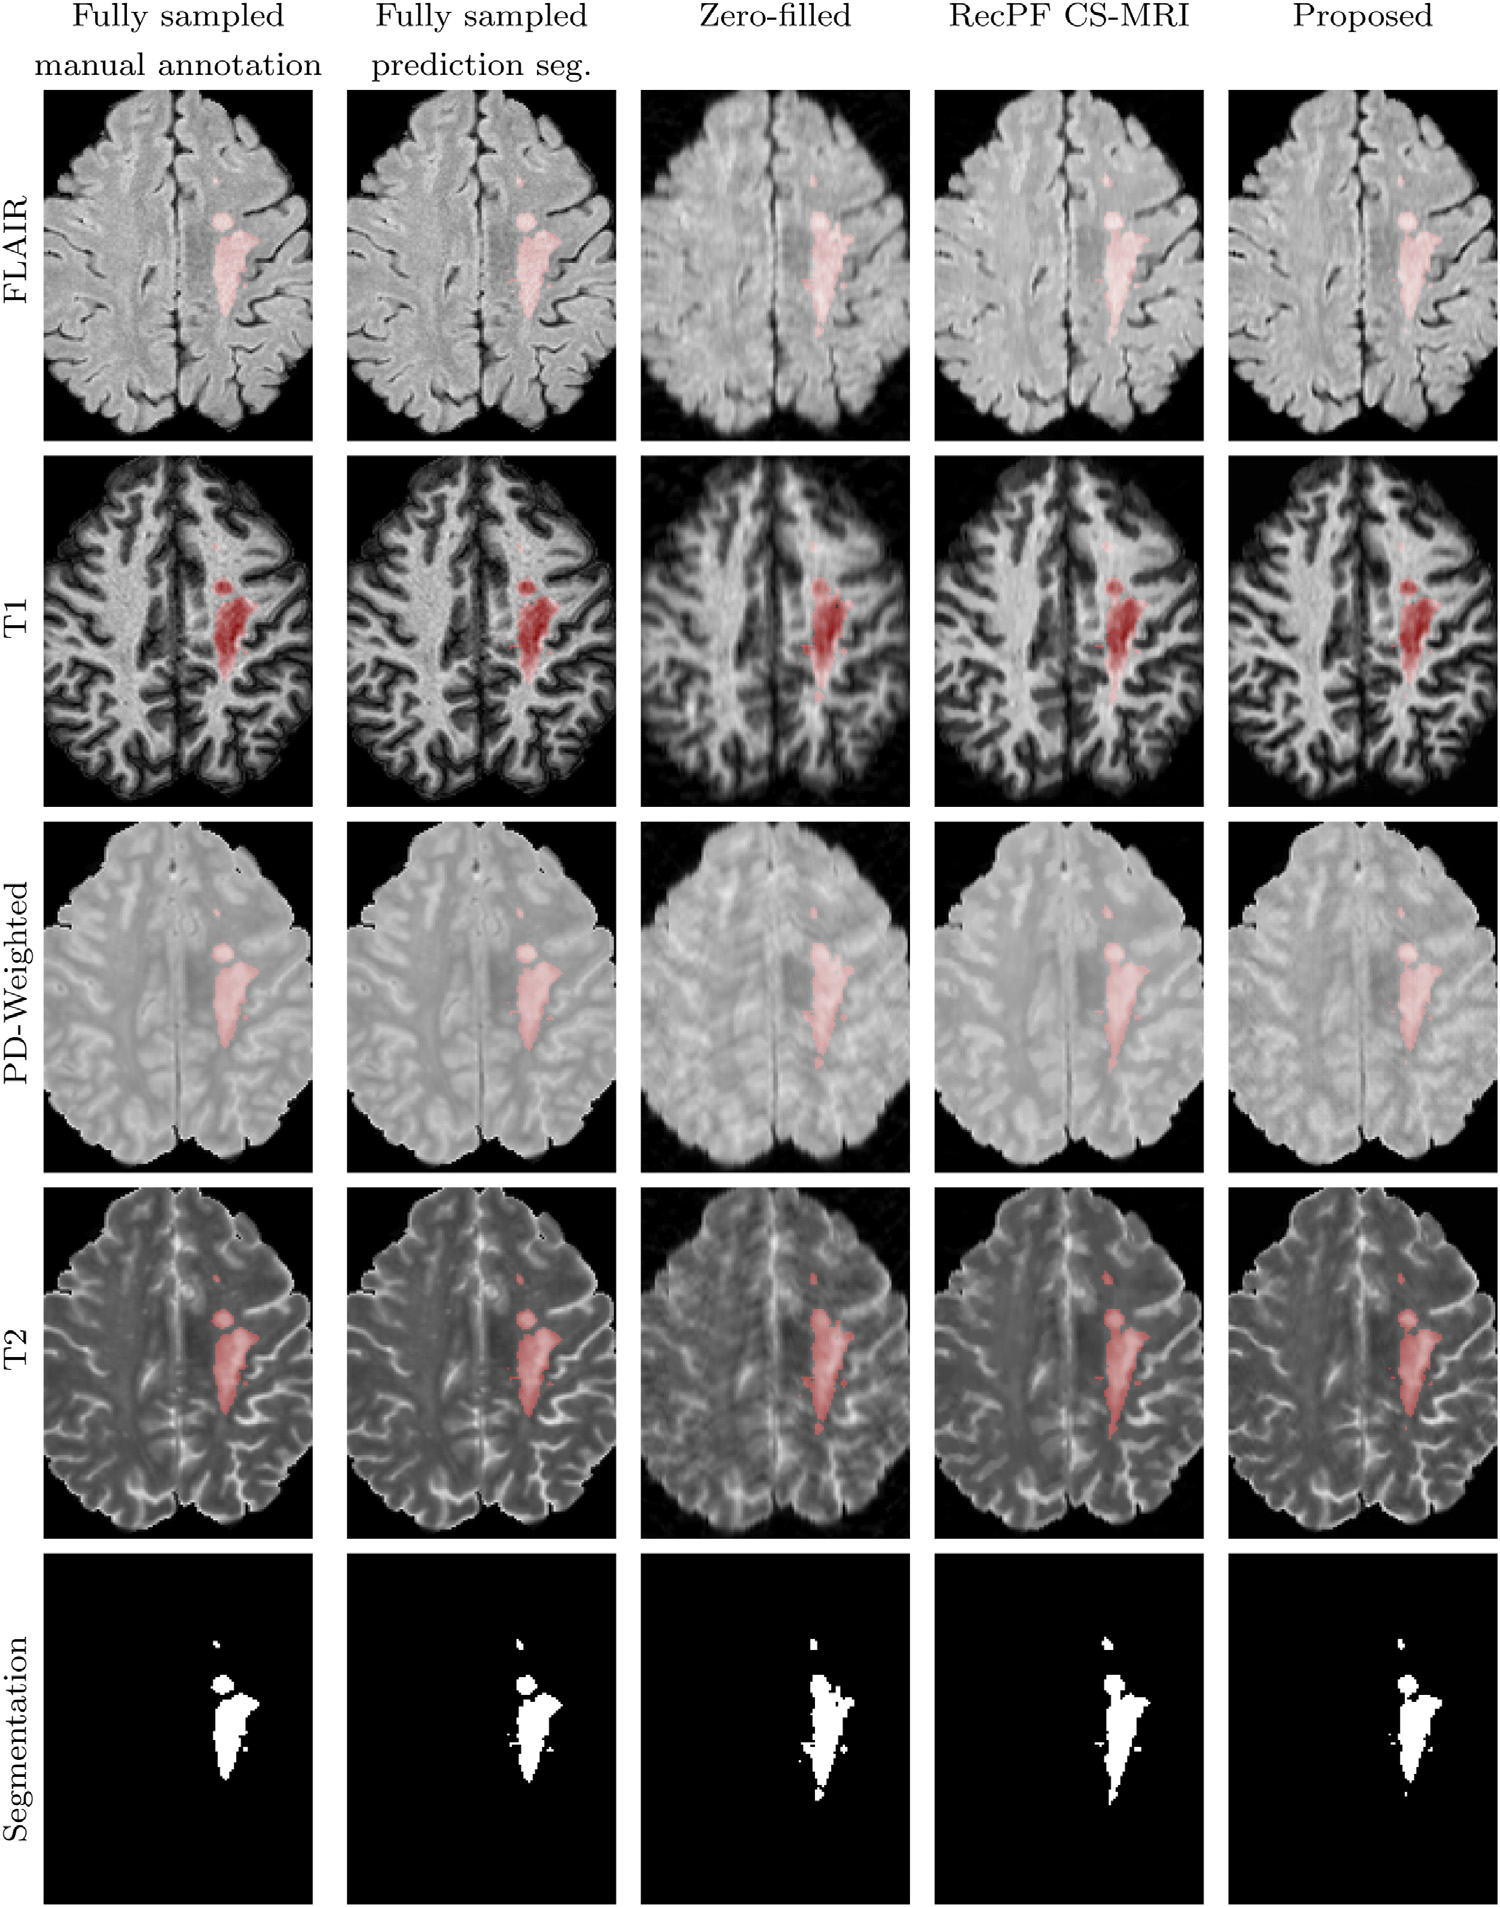

In addition, in order to show the clinical availability of reconstruction results, the authors performed lesion segmentation, which is based on a DL tool presented by Shwartzman et al [8]. The authors also provide manual segmentation as a reference (Ground Truth). A visualized result is shown in Figure 4. The quantization results in Table 5 first compare the segmentation results of the Shwartzman's tool with the GT, and then compare the segmentation results of the reconstructed image using the DL tool and the fully sampled image using the DL tool.

Figure 4: Annotations and the lesion segmentation based on reconstructed scans